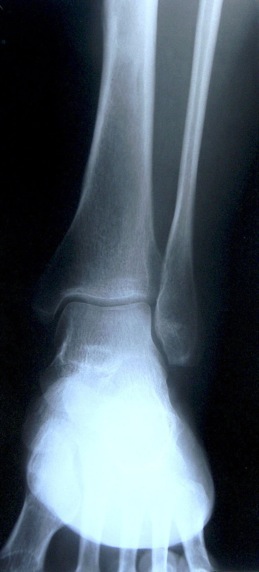

Analyse de radiographies

Analyse différentes radiographies. Essaye de reconnaître:

les différentes parties représentées: os, articulations,...

les malformations, les déplacements, les fractures.

l’âge des sujets: zones de croissances.